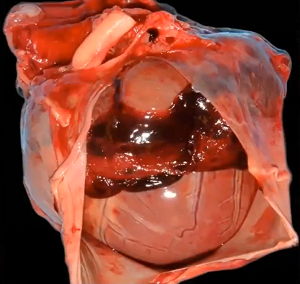

As the diseased mitral valve

degenerates, myxomatous transformation -- the development of excess gel-like connective

tissue between the cells of the leaflets, the extracellular matrix -- causes the valve to lose its flexibility, its

leaflets thickening and shortening, its fibers stiffening, and its

chordae tendineae elongating. The leaflets develop nodules which appear

greyish white, smooth, and glistening, as

if filled with fluid. As they

increase in number and size, their effect upon the chordae tendineae and

the function of the valve worsens. (See image at right, from this

March 2012 article.) These nodules, called lesions, are

graded according to their severity from Type I to Type IV, called the

"Whitney grades". See this

August 1974 article for their details. See, also, this

January 2010 article for a more detailed description of the changes

in the valve leaflets as MVD progresses.